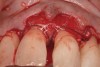

Fig. 17  A significant intrabony defect around tooth No. 27.

Figure 17

Fig. 18  Subgingival calculus and severe bone loss.

Figure 18

In a case with an intrabony defect, such as with the patient in Figure 17, a periodontist might suggest sacrificing supporting bone to remove the osseous defect. Doing this might lead to issues related to tooth mobility, esthetics, caries, and hypersensitivity.

The patient had been referred for an implant consultation for the mandibular right canine. She had very deep probing depths on the lingual. When the flap was raised, a significant amount of subgingival calculus was seen as a local risk factor (Figure 18). However, she had no significant pathology to remove from the situation. Debridement was performed the same as in Case 3 with the rotary ultrasonic and manual instrumentation.

The defect was obturated with mineralized freeze-dried bone and hydrated with platelet-derived growth factor. As with any growth factor, when implementing it clinically, all growth factors require a carrier to bring that growth factor to the desired site, which do not elicit an inflammatory response. In this situation, it is the mineralized freeze-dried bone allograft. This combination was demonstrated by Rosen et al8 to be efficacious in treating intrabony defects. A biologic approach was taken both in terms of the graft and membrane (Figure 19). Primary closure was achieved.